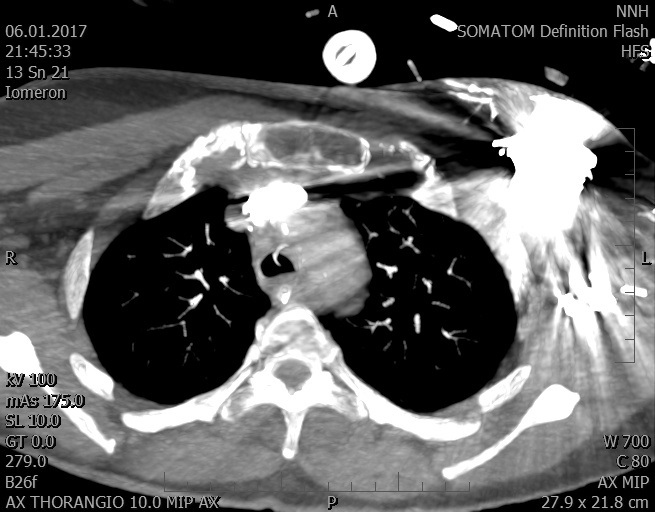

Video 2 - Echokardiograficky byla zjištěna těžká dysfunkce dilatační levé komory s nezvětšenou pravou komorou.Pro nejasnou příčinu zástavy jsme provedli i vyšetření výpočetní tomografií (CT), které vyloučilo plicní embolizaci (série 1 - soubory na konci článku). V den přijetí při přetrvávající oběhové nestabilitě byla nemocná opakovaně defibrilována pro fibrilaci komor se stabilizací rytmu po podání amiodaronu a mesocainu. Dle hemodynamických měření se jednalo o těžký kombinovaný šok. Vstupní laboratorní vyšetření bylo bez větších pozoruhodností. Posléze jsme doplnili anamnézu od příbuzných a zjistili, že pacientka užila do dvou hodin před srdeční zástavou první tabletu amoxicilinu na lehký respirační infekt. Při nevýtěžnosti vstupních vyšetření a nových anamnestických informacích jsme doplnili 14 hodin po kolapsu vyšetření koncentrace tryptázy v séru, která byla extrémně zvýšena (tabulka 2), což nás vedlo k podezření na anafylaxi.